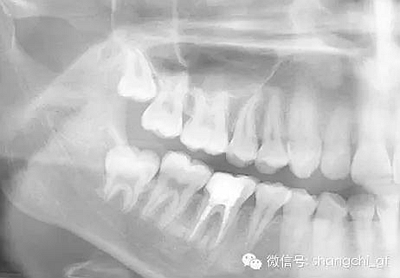

1.拍一張需要去除纖維樁的牙齒的X光片,仔細(xì)估算樁的長度,直徑。

4.用匹配的鉆石擴(kuò)大至最初的直徑,用X光檢查。

5.重新安裝新的樁核等材料。通過X光片檢查以上步驟。

手術(shù)前

手術(shù)后